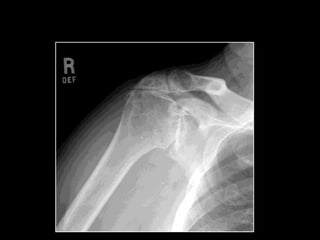

ROTATOR CUFF ARTHROPATHY

• Cuff Tear Arthropathy (CTA)

• Irreparable Massive cuff tear in elderly

• Osteoarthritis with cuff tear in elderly